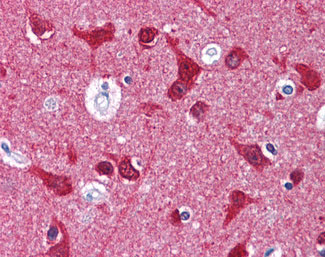

Anti-MAPT / Tau antibody IHC of human brain, cortex.